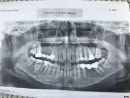

Глядя на ортопантомограмму Вам необходимо обратиться к стоматологу-терапевту для перелечивания, практически всех с пролеченных каналов, так как каналы запломбированы не полностью.

На нижней челюсти из-за долгого отсутствия шестого зуба, седьмой наклонился в сторону дефекта. В идеале надо выло восстановить его положение у ортодонта, а после проводить протезирование.